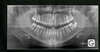

• Des anomalies prévisibles peuvent être détectées dès l'apparition de la première dent définitive (première molaire mandibulaire) voire avant. Guider les éruptions ultérieures, modeler précocement les arcades et d'autres gestes peuvent simplifier le traitement.

Une prise en charge précoce permettra de mettre en jeu toute la panoplie d'outils permettant de corriger des anomalies dentaires et osseuses et aussi réaliser une orthodontie fonctionnelle.